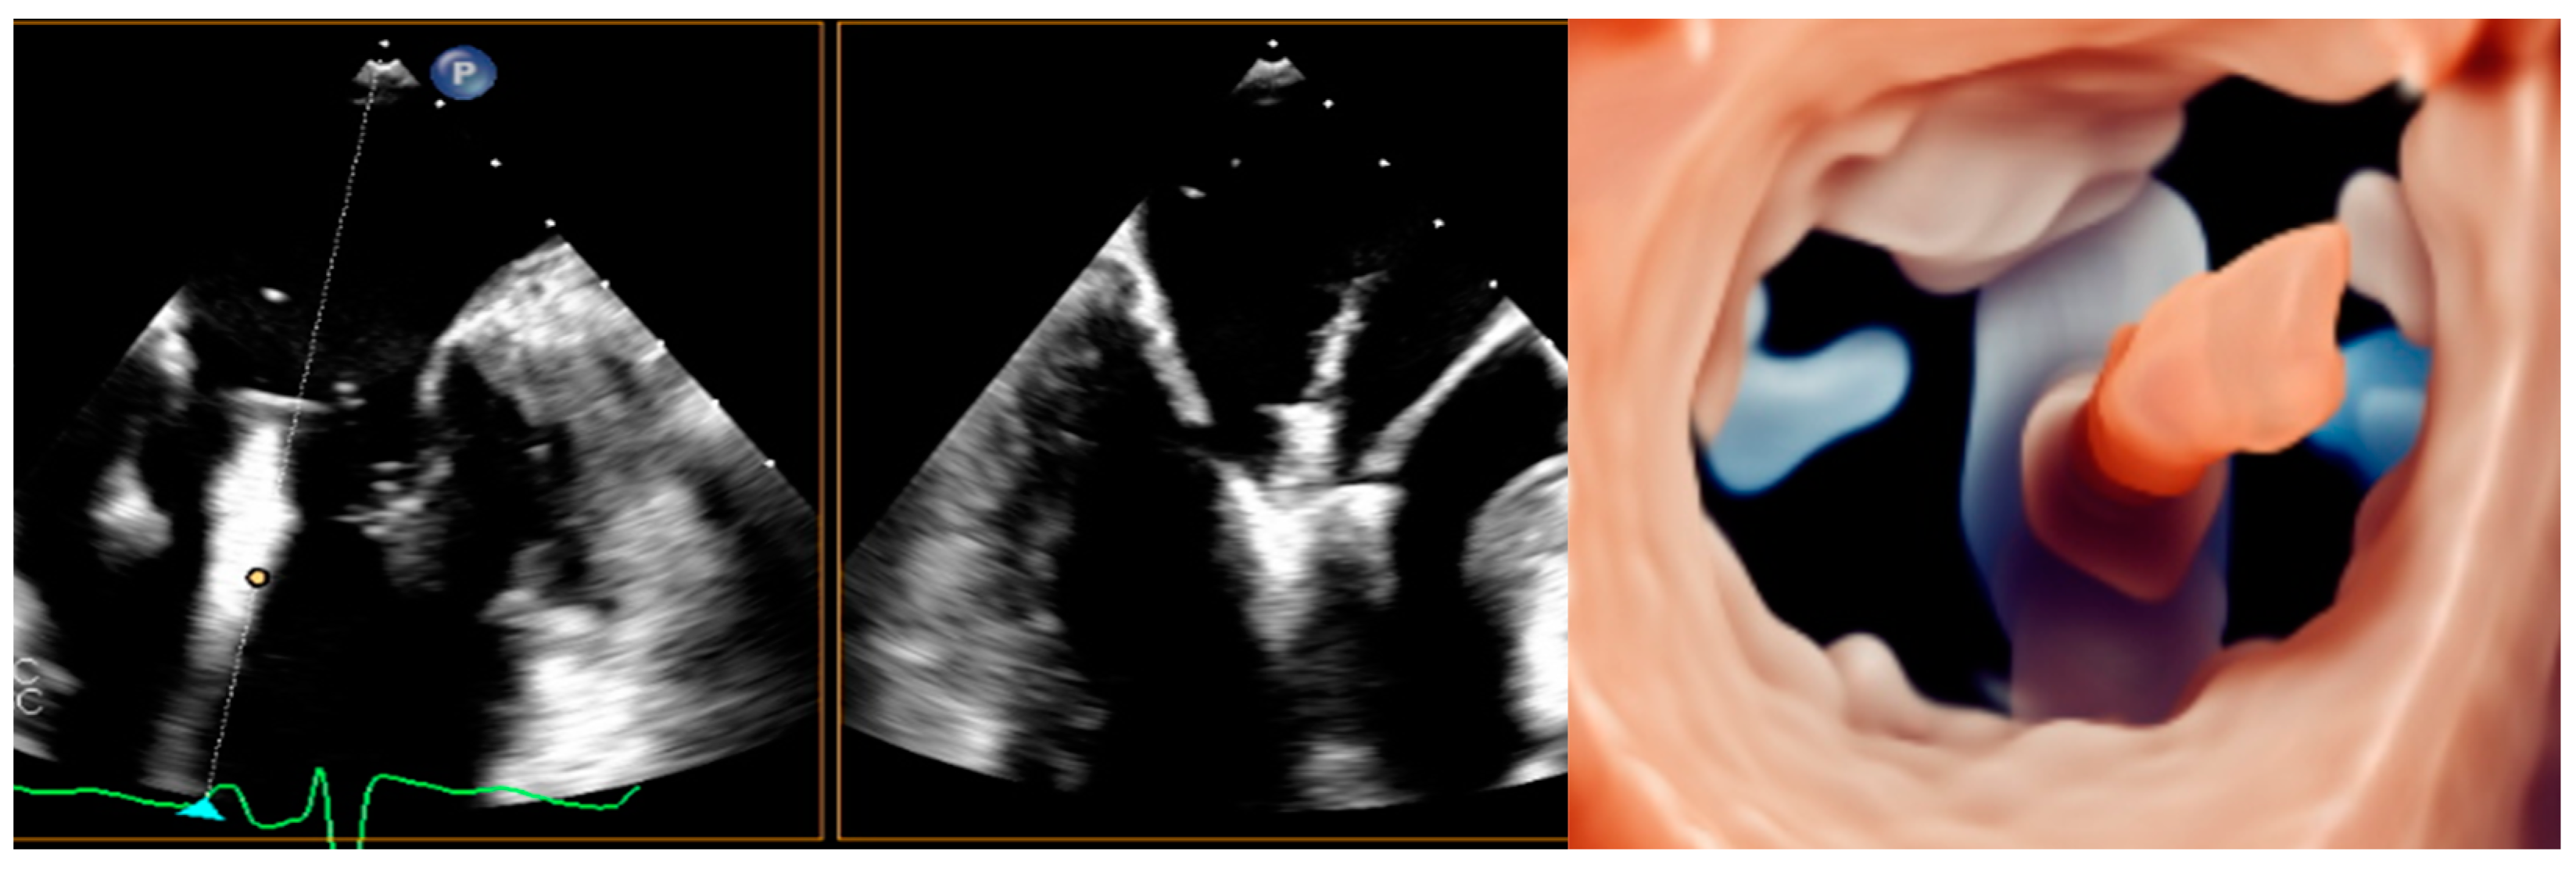

5.1. Transcatether Edge-to-Edge Repair

5.5. TMVR